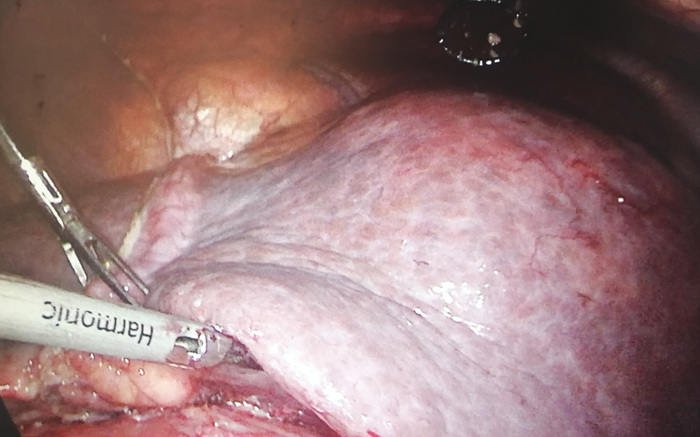

这个让人大吃一惊的巨大恶性肝肿瘤,在鹤山市人民医院普外科历时5个小时的努力下成功切除,这是我院普外科首例自主完成的腹腔镜标准左半肝(肝巨大肿瘤)切除术,标志着我院在微创治疗技术上迈上了新的台阶。

普外科医护团队经过详细的会诊分析,并征求患者同意,决定行腹腔镜下手术切除肿瘤。由于此类手术难度大、风险高、并发症多,为了确保手术顺利进行,普外科、影像科、手术麻醉科等学科多次组织进行术前讨论,精心制定具体手术方案、麻醉方案以及术中术后各种应急预案,并进行了充分的术前准备。

10月26日,在普外科、手术麻醉科的精心配合下,范海鹰副主任、任伟耀副主任医师在手术室经过近5小时奋战,完整地切除左半肝巨大肿瘤,重达1.5公斤,术程顺利,术中出血少,患者术后恢复良好,病理结果为中-低分化肝细胞癌。

独立开展的手术成果来之不易,对于普外科既是挑战更是突破。手术的成功开展,离不开良好的腹腔镜技术、慎密的术前准备、娴熟的手术技巧和完美的团队配合,随着我院微创技术的不断精进,未来将为鹤山地区肿瘤患者的治疗和康复带来新的希望。